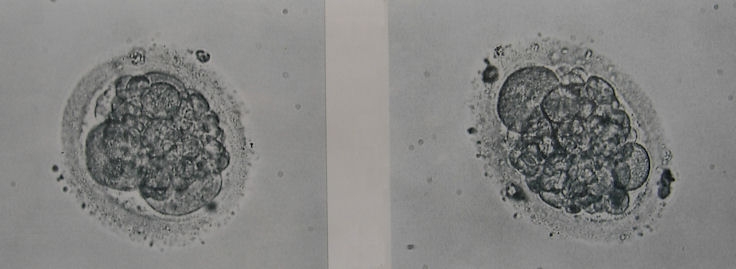

Laut meinen Recherchen im Internet wäre es D-Qualität mit vielen Fragmentierungen!?

In der Klinik wurde sich nicht weiter dazu geäussert, würde gern mal Ihre Beurteilung dazu hören!

Wieviel Zeller sind das?

Welche Qualität?

Zuviele Fragmentierungen?

ja, es sind schon deutliche Zeichen von starker Fragmentierung zu sehen. Insgesamt sind sie deshalb schwer zu klassifizieren. Da wir aber wissen, dass Embryonen immer nur in einer Momentaufnahme fotografiert werden und sich Fragmente u.U. sehr schnell resorbieren und umstrukturieren, muß der Embryoscore in Bezug auf die SS - Chance nicht allzuviel bedeuten. Also Abwarten und Tee trinken (ich weiß, sagt sich leicht....)